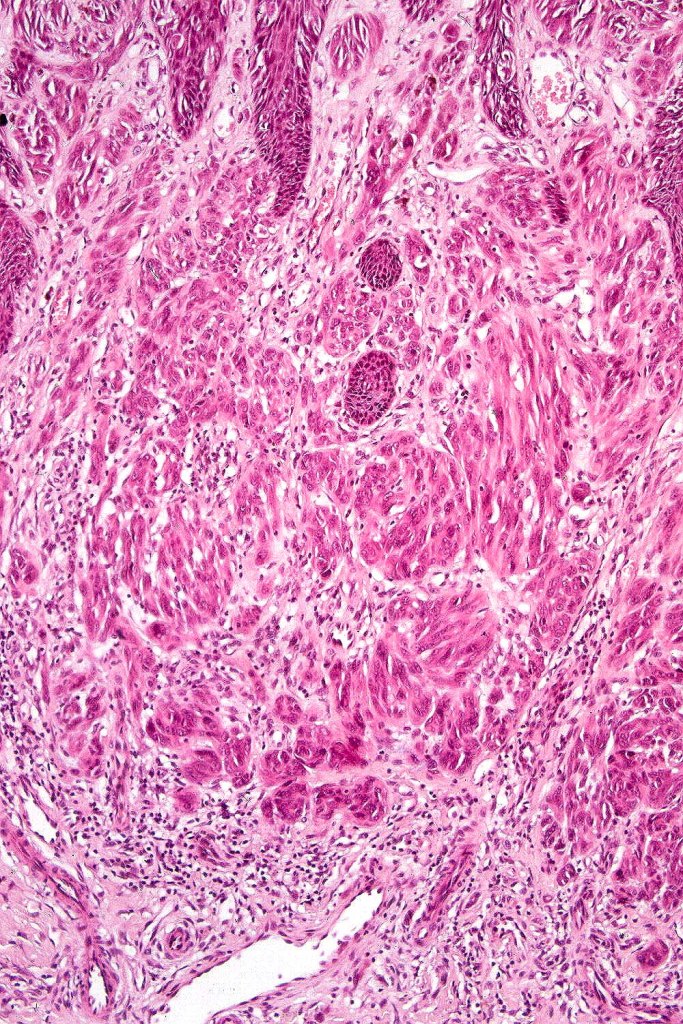

•Junctional nests often vertically orientated, dyscohesive with a surrounding retraction artifact

•Pleomorphism is almost invariable but affects all of the population to the same extent i.e., the cells & nuclei all look very much the same

•Spindle cell nests often display a “raining down” growth pattern

•Spindle cells have abundant cytoplasm and vesicular nuclei with small nucleoli

•Mitoses can brisk in younger patients and should not be taken as indicating melanoma

•Mitoses are restricted to the superficial aspect on the nevus and are never atypical

•Kamino bodies (often multiple) are a characteristic feature